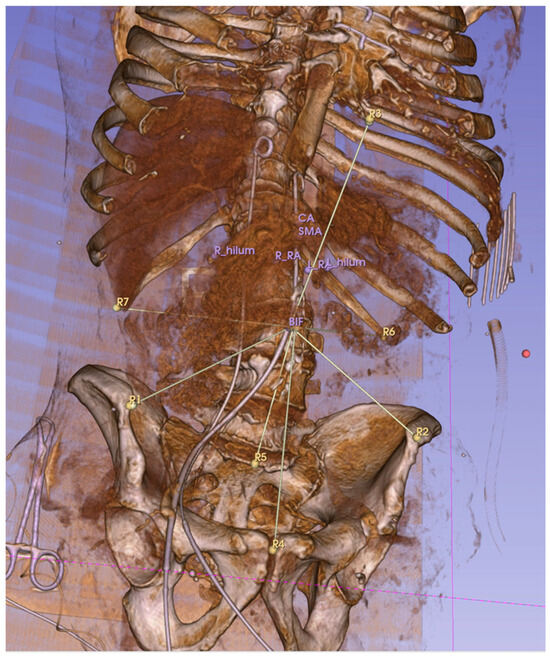

Distances between the anatomical reference landmarks and targets were measured using an open-label extension of 3D Slicer, called “Fiducials To Model Distance”. The measured Euclidean distances then were compared to each other between scans with different pressures/positions. All the scans performed in the same PP with different IAPs were compared to reveal the effect of IAP (base was zero mmHg). Then, all the scans with the same IAP but different positions were compared to show the effect of PP (the base was the supine position).

Distances were calculated between each reference landmark and the target (see Figure 3). These distances were then compared between scans. For example, to calculate the effects of 15 mmHg IAP in the supine position, we measured the distance of targets to reference points in the CT scan done in the supine position at 0 mmHg and 15 mmHg. To measure the displacement of a target organ, we took the average of the absolute differences in distance to the reference point between the baseline scan (0 mmHg, supine position) and the one at 15 mmHg.

Figure 3. Euclidean distances between reference points (R1–R7) and target anatomical locations were measured. This 3D, reconstructed CT image shows the measurement lines connecting the aortic bifurcation to the reference landmarks R1–7. The distal tip of the sternum (R3 here) was later excluded due to its broad movement associated with the abdominal pressure increase.